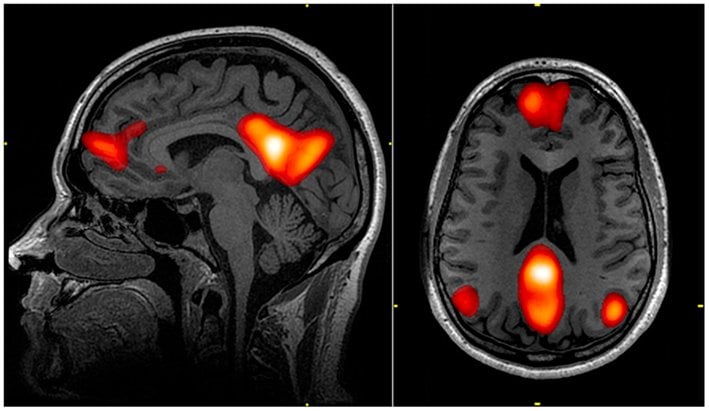

However, one thing that is common in all cases is that, although day-dreaming can potentially occur under any circumstance, it’s more likely to happen when a subject feels a slight, temporary disconnection from his primary task. Another hypothesis is that spacing out activates the Default Mode Network, a network of interacting brain regions that are mostly distinct from other areas of the brain, but are highly correlated to each other.

the DMN

Regions of the default mode network as visible in a fMRI scan (Image Credit: John Graner / Wikimedia Commons)

This part of the brain is activated when someone is at “wakeful rest”, i.e. not focused on what’s going on around them. The DMN is frequently activated when one thinks about their past or future, or when they are having a particularly introspective moment!

Part of why the default mode network has that name is because it activates by ‘default’ when an individual is not strongly involved in a given task. As you might have guessed, the DMN is negatively correlated with the attention networks of the brain. So, just because a person appears super-attentive doesn’t mean they’re actually paying attention.